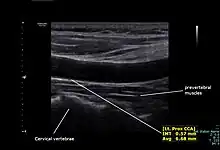

The condition and health of the common carotid arteries is usually evaluated using Doppler ultrasound, CT angiography or phase contrast magnetic resonance imaging (PC-MRI).

Typically, blood flow velocities in the common carotid artery are measured as peak systolic velocity (PSV) and end diastolic velocity (EDV).

In a study of normative men aged 20-29 years, the average PSV was 115 cm/sec and EDV was 32 cm/sec. In men 80 years and older, the average PSV was 88 cm/sec and EDV was 17 cm/sec.[6]